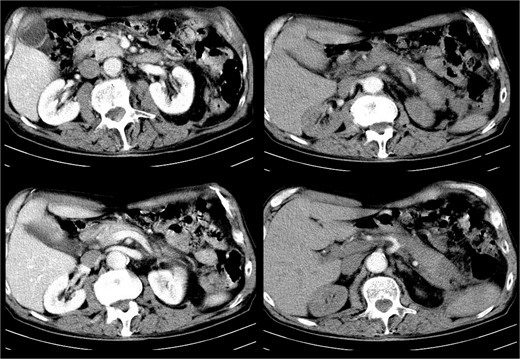

Nine days later, a persistent fever reaching 38.6°C with tenderness in upper abdominal quadrants was presented. In addition, the patient reported significant fatigue and exhibited tachycardia with a heart rate of up to 106 beats per minute. Laboratory findings revealed leukocytosis (15.03 G/L) with neutrophilia (11.84 G/L), moderately elevated serum amylase (394 U/L), and hyperbilirubinemia (total – 31.7 μmol/L, direct – 23.1 μmol/L). Abdominal ultrasound showed an enlarged pancreas with blurred, heterogeneous hypoechoic echostructure, indistinct gland margin, peripancreatic fluid, and walled-off necrosis next to the pancreatic tail, extending laterally to the splenorenal recess, with a longitudinal size of ~10 cm and thick heterogeneous content, suggesting secondary inflammation. Computed tomography (CT) verified gas-containing fluid collections spreading from the pancreas to the left iliac crest (Fig. 1A and B) along with bilateral pleural effusions.

CT image of large infected peripancreatic collections with multiple air locules (A and B) and placed pigtail catheters post-imaging (C and D).

Following well-established guidelines, empiric antibiotic therapy with a carbapenem was started (Meropenem 1 g every 8 hours). The patient underwent PCD with the initial insertion of five drains: two in the peripancreatic collection and three in the pararenal space, with one situated caudal to the lower border of the collection at the level of the iliac crest. Microbiological examination revealed the presence of Meropenem-resistant Escherichia coli, sensitive to Cefoperazone-sulbactam, necessitating a change in antibiotic treatment according to antibiogram results. Continuous postprocedural transcatheter lavage with physiological saline was performed. Follow-up abdominal sonography showed the persistence of a small undrained collection in the posterior pararenal space, leading to the placement of two additional drains in that area (Fig. 1C and D).